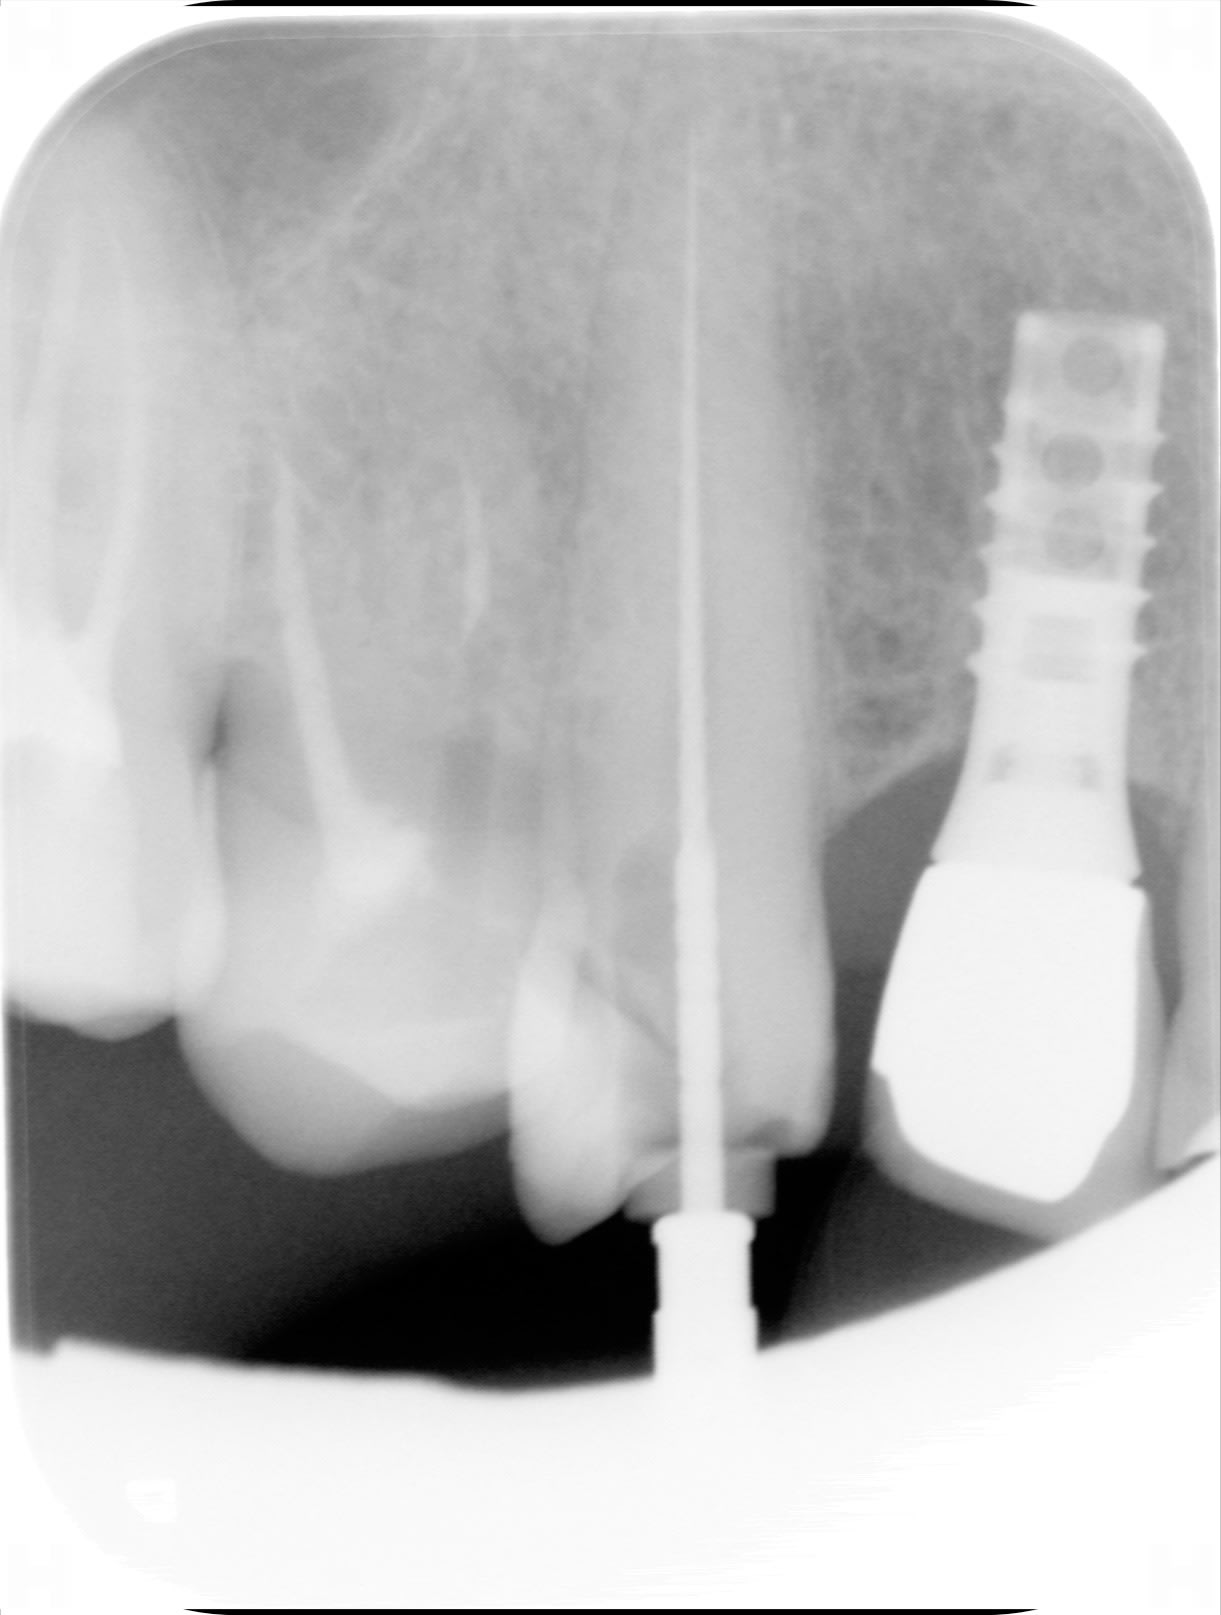

ci joint un implant dont pilier et couronne sont dévissés

Une idée pour que je puisse renouveler l'accastillage ?

Non c’est un paragon core vent wide en 4,5mm (l’ancêtre du zimmer)

Ah oui tu as raison....c’est bien un straumann

Oui straumann....donc octogone interne, vis hexagone 1.25mm

C’est bizarre ce que tu me dis parceque le pilier , je l’ai eu en main et il a une connexion conique sans hexagone ni octogone , je l’ai dévissé en tournant la dent ....pardon , l’ensemble couronne /pilier que j’ai pas réussi à désolidariser...